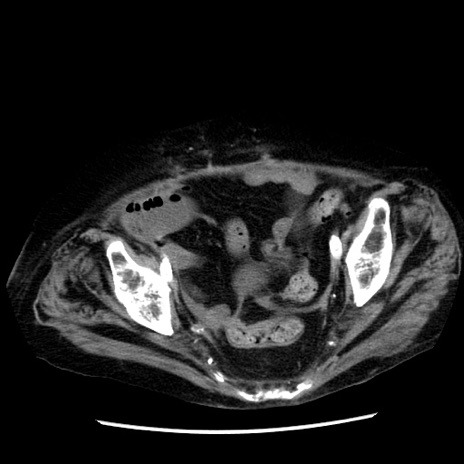

冠状断像

【症例】 90歳代女性

【主訴】 腹痛・嘔吐

【現病歴】今朝から左側腹部痛を認めた。 経過観察していたが、嘔吐を認めたため来院。

【既往歴】 子宮癌術後

【身体所見】 意識清明、BP 127/54mmHg、P 98bpm Sp02 95%(RA)、BT 35.8°C、腹部平坦・軟腸ぜん動音聴取良好、右下腹部圧痛(+) 反跳痛なし

【データ】WBC 9800、CRP 0.46